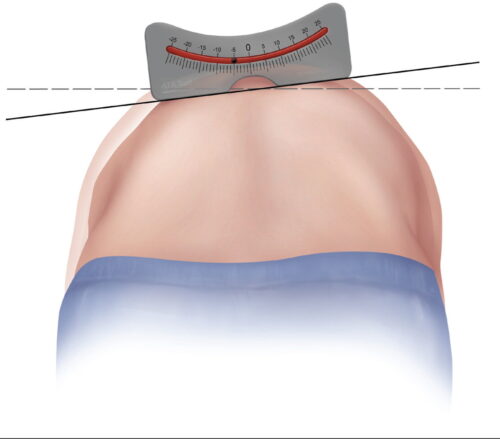

كيف يتم قياس زاوية كوب؟

تصوير الأشعة: يُجرى للمريض وهو واقف أو مستلقٍ.

تحديد الفقرات النهائية: اختيار الفقرة الأكثر ميلًا في أعلى وأسفل الانحناء.

رسم الخطوط: رسم خطين على الفقرات المائلة ثم قياس الزاوية الناتجة.

يتميز هذا القياس بالدقة، لكنه قد يتأثر ببعض العوامل مثل: وضعية المريض، اختلاف تقييم الأطباء، ودوران الفقرات.

طريقة زاوية دوران الفقرات : بديل واعد بدقة عالية تصل إلى ±3 درجات.